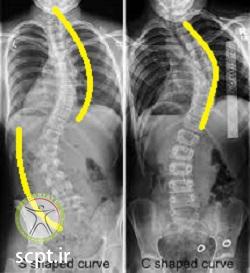

به طور کلی اسکولیوز ها از لحاظ شکلی و تنوع آن به دو شکل C و S تقسیم می شوند. همانطور که در شکل های زیر می بینید در شکل سمت راست تحدب توراسیک یا مهره های پشتی به سمت راست وجود داشته و یک شکل انحنا مطابق خط زرد ایجاد شده است که به شکل C برعکس می باشد ولی در شکل سمت چپ دو انحنا ایجاد شده که در مجموع به شکل S ایجاد شده است.